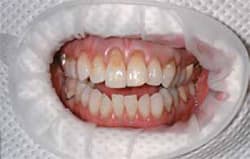

| Isolation of the treatment area.(View Figure) | Composite resin shade selection was performed to achieve the desired result.(View Figure) | ||||||

| Final result after bonding with BeautiBond and Beautifil II(View Figure) | In-treatment view of the direct resin restorations performed with BeautiBond and Beautifil II.(View Figure) | ||||||